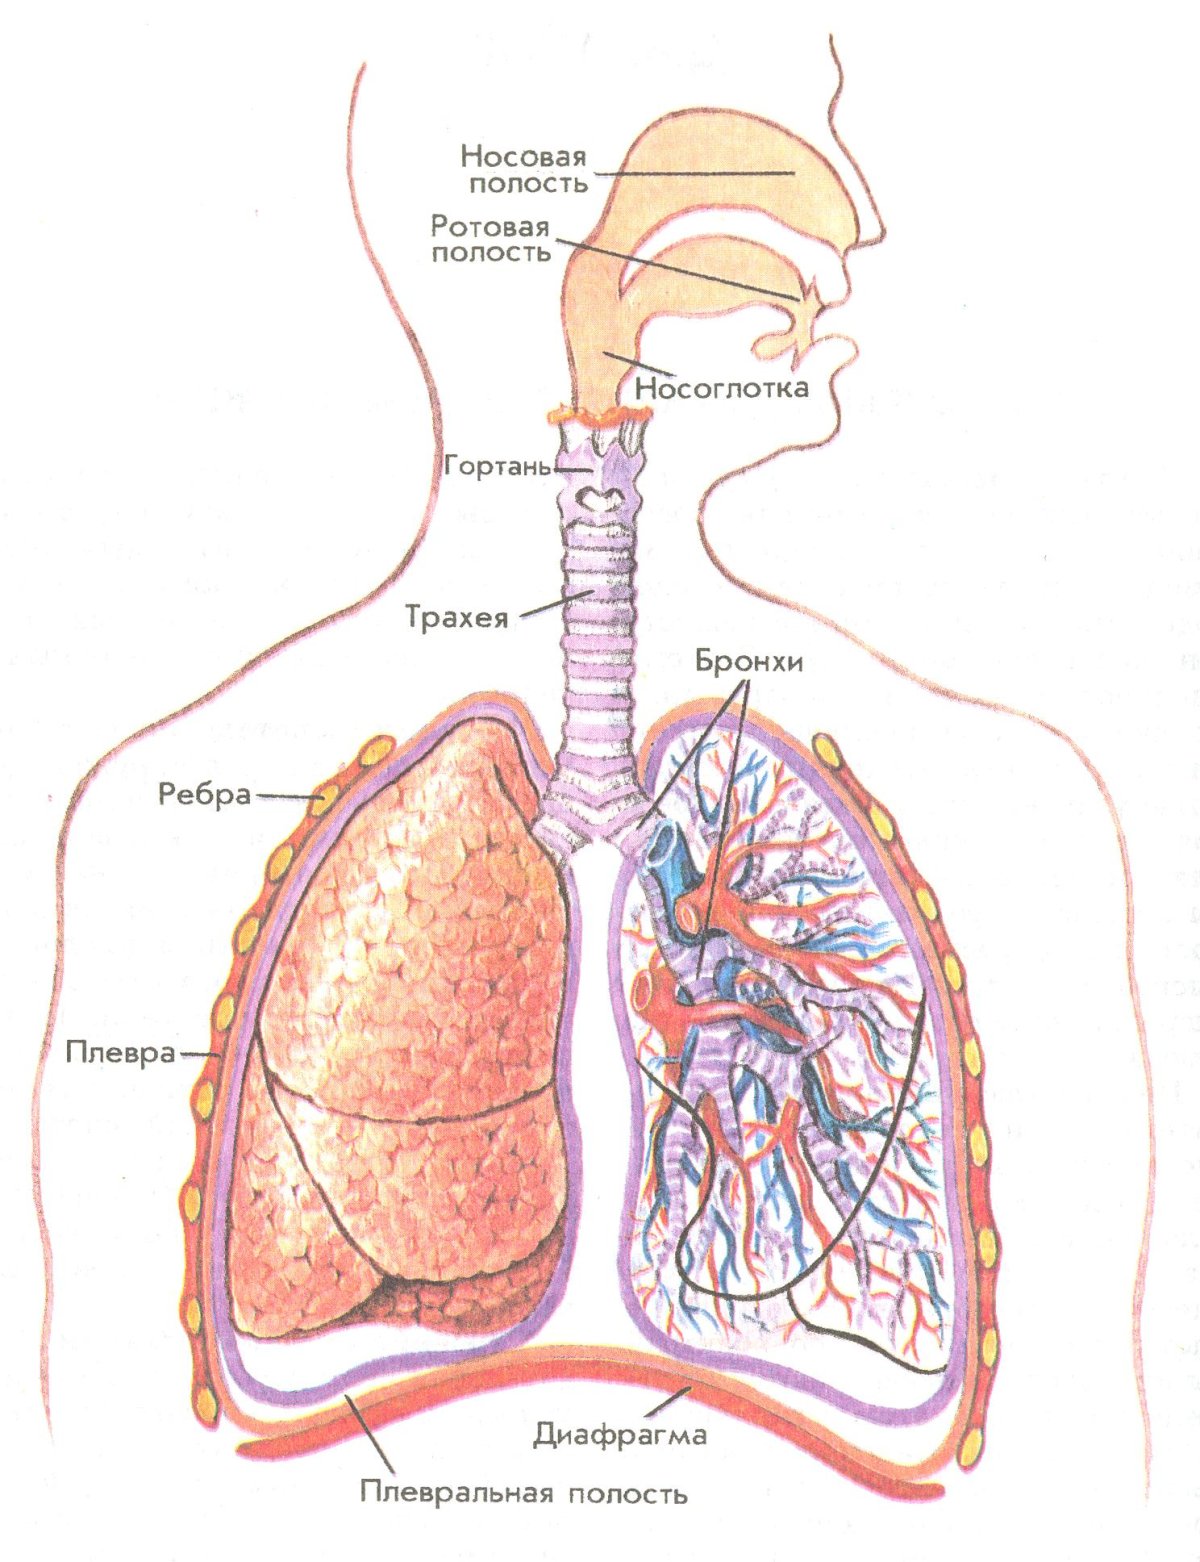

Еда для Легких и Бронхов - Полезные Рецепты